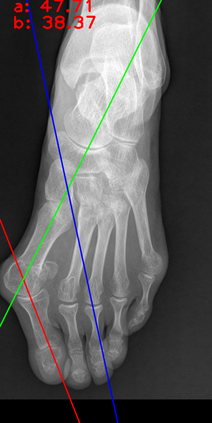

Angular measurements is essential to make a resonable treatment for Hallux valgus (HV), a common forefoot deformity. However, it still depends on manual labeling and measurement, which is time-consuming and sometimes unreliable. Automating this process is a thing of concern. However, it lack of dataset and the keypoints based method which made a great success in pose estimation is not suitable for this field.To solve the problems, we made a dataset and developed an algorithm based on deep learning and linear regression. It shows great fitting ability to the ground truth.